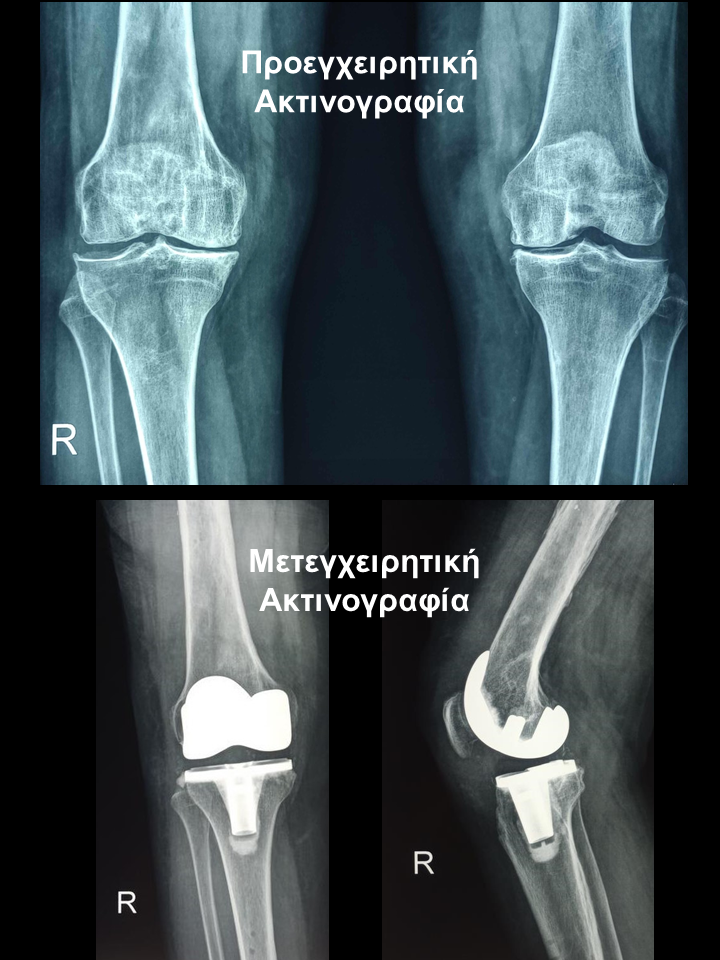

Ασθενής 61 χρονών με ιστορικό ρευματοειδούς αρθρίτιδας

Ασθενής  61 χρονών με ιστορικό ρευματοειδούς αρθρίτιδας. Είχε υποβληθεί πριν χρόνια σε αρθροπλαστική δεξιού γόνατος με τη συμβατική τεχνική. Στην παρούσα φάση λόγω προσβολής του αριστερού γόνατος που της προκαλούσε έντονο άλγος υπεβλήθη σε ρομποτική αρθροπλαστική στο αριστερό γόνατο. Χρησιμοποιήθηκε η τεχνική διατήρησης οστού όπου αφαιρέθηκαν λιγότερα χιλιοστά οστού. Ο άξονας στο αριστερό γόνατο από 20 απόκλιση και έλλειμα έκτασης 20 αποκαταστάθηκε στις 00 και η  κάμψη στο αριστερό αποκαταστάθηκε στις 1200 . Η ασθενής βαδίζει πλέον χωρίς καμία ενόχληση.